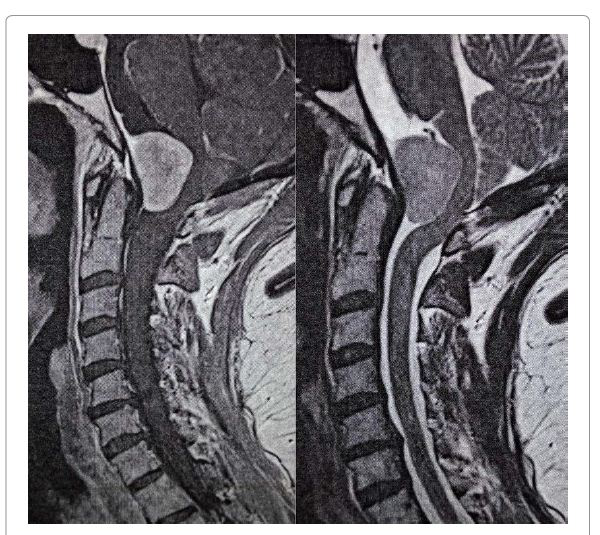

经过仔细详细的病史和体格检查,她还报告了较近(几周)发作的轻度吞咽障碍(吞咽困难)和左颊和舌头微微麻木。她接受了脑部和颈部磁共振成像(MRI)扫描,发现前部有肿块(T1上为等强度,T2上为高强度,弥散加权序列上为低点,具有均一的对比度增强,清晰的边界和特征性硬脑膜尾巴)大孔的边缘压缩长延髓并向后移位(图1和图2)。

病变的较大尺寸为21mm(前后),28mm(横向)和28mm(垂直)。枕骨大孔尺寸为35毫米(前后)乘28毫米(横向)。术前数字减影血管造影显示肿瘤是由左侧咽升动脉提供的。

图1:术前矢状位对比增强的T1WI和T2WIMRI扫描